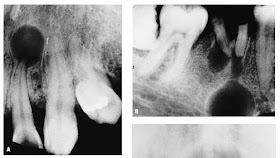

Radicular cysts (see Figure 7-21, A and B) derive from inflammatory proliferation and cystic degeneration of epithelial cell Malassez rests contained in periapical granulomatous tissue, usually secondary to pulp necrosis. When this change occurs in a granuloma that has not been eliminated by tooth extraction, the cyst is no longer associated with the apex of a tooth and is customarily referred to as a residual cyst. Radicular cysts are the most frequent type of jaw cyst and make up as much as 55% of jaw cysts in some series (once again, the difficulties of determining if a given radiolucency is a cyst, a granuloma, or some other lesion influence the validity of the estimates given for different series). There is a large body of literature devoted to elucidating the mechanism and cause of the epithelial proliferation, fluid accumulation, bone resorption, and expansion that underlie the development of radicular cysts.The odontogenic keratocyst (formerly, primordial cyst)(Figures 7-23 and 7-24; see also Figure 7-20, B, and

The nasopalatine (incisive canal) cyst (see Figure 7-21, D) is derived from remnants of epithelium-lined vestigial oronasal duct tissue and possibly also from Jacobson’s (vomeronasal) organ, which is said to account for the occasional finding of pigmented cells in the wall of these cysts. On the basis of radiographic surveys of dried skulls, the frequency of this cyst has been described as being as high as 1.8% although differences of opinion as to the maximum size the image of the incisive canal may attain without being considered cystic raise doubt as to the validity of this figure.The surgical removal of a nasopalatine cyst commonly produces loss of sensation and paresthesia of the anterior palate supplied by the nasopalatine nerve; thus, unequivocal signs of cystic swelling in the canal are required before exploration of the area or excision of a suspected cyst is undertaken.

Cysts of the maxillary sinus (see Figure 7-21, C) were thought to arise from pseudostratified columnar respiratorytype epithelium rather than from the oral mucosa, but they are of interest because of the frequency (as high as 2.6% in one series)with which they are recognized in panoramic dental radiographs, which demonstrate them more efficiently than the traditional Waters’ projection.In reality, most of these dome-shaped radiopacities of the sinus floor are nothing more than inflammatory polyps and are not true “retention” cysts. Cysts and odontogenic tumors arising in the maxilla, especially molar and premolar radicular cysts, may extend into the maxillary sinus but usually do so by expanding the floor of the sinus ahead of them.Cystic degeneration may also occur in benign odontogenic tumors, but the hamartomatous or neoplastic nature of odontogenic tumors requires that they be given special consideration (see following section). The misleading socalled cystic radiographic appearance of many odontogenic tumors (reflected in the synonym “multilocular cyst” for ameloblastoma), the majority of which develop within and expand the jaw, has also led to clinical confusion between the two classes of lesions.Cystic degeneration is a common change in odontogenic tissue, and it is not surprising that odontogenic tumors frequently contain cystic areas. The importance of a thorough histopathologic examination of all curetted material is once again underlined by the fact that tumor tissue may be recognized in only a small section of a lesion, the bulk of which is represented by a relatively nonspecific odontogenic cyst.